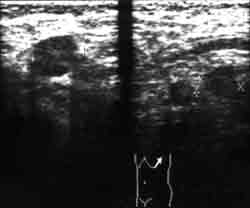

Рисунок. Метастатические лимфатические узлы при УЗИ характеризуются следующими признаками: бугристый наружный контур, неоднородная структура за счет наличия участков гетерогенной плотности, уплотнения в виде тяжей и рубцов, а также наличие жидкостных участков различной формы и размеров. Сонограмма аксиллярной области. Метастазы рака молочной железы в лимфоузлы.